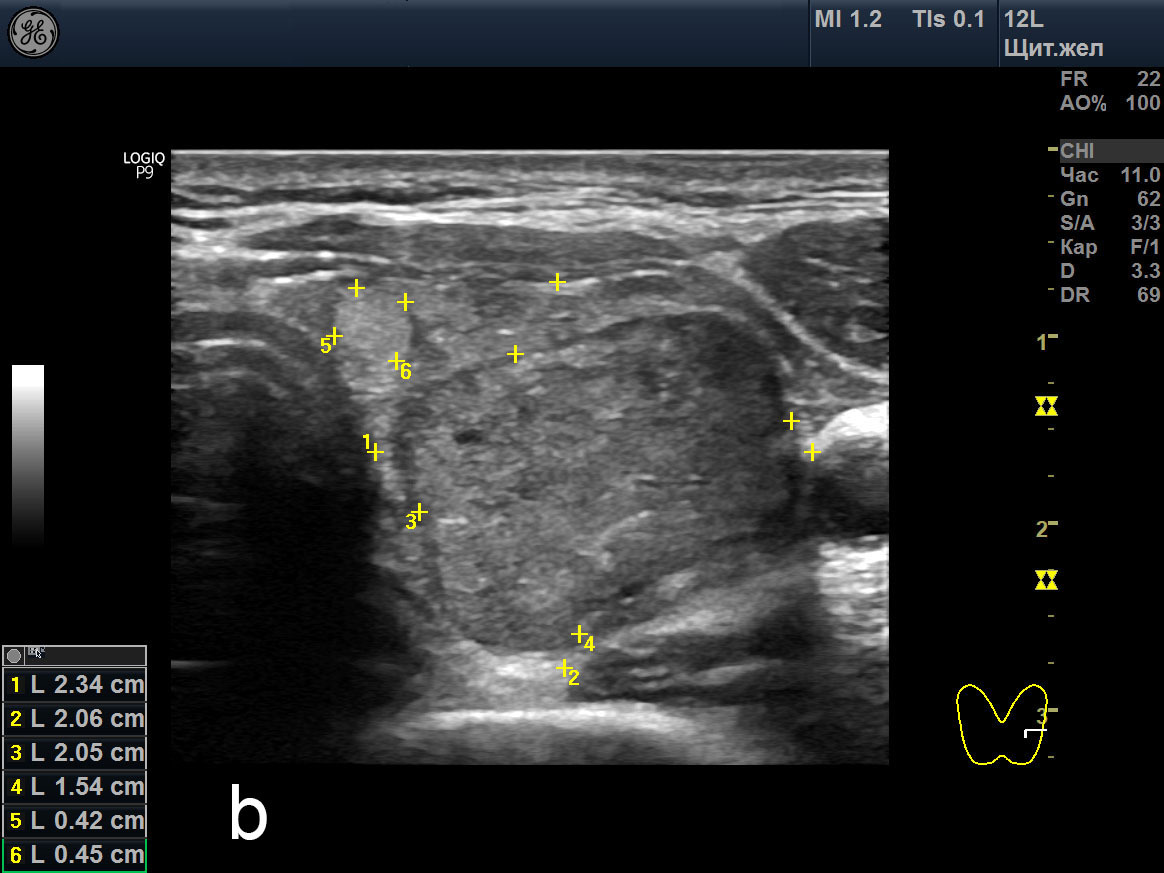

Узлы в щитовидке симптомы